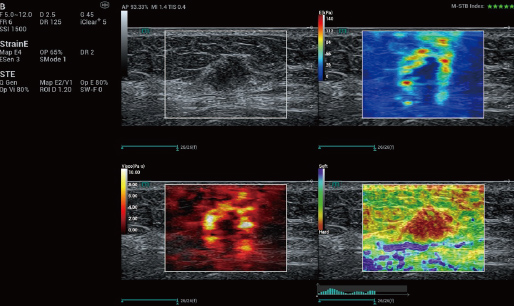

STVi consente la valutazione quantitativa della viscosit├Ā dei tessuti e fornisce immagini multiparametriche in tempo reale, offrendo un approccio pi├╣ completo alla diagnosi per immagini e all'analisi quantitativa di malattie epatiche croniche, lesioni mammarie e altre condizioni.

Valutazione della malattia epatica cronica

Strumenti di quantificazione multipli

Valutazione del tumore al seno